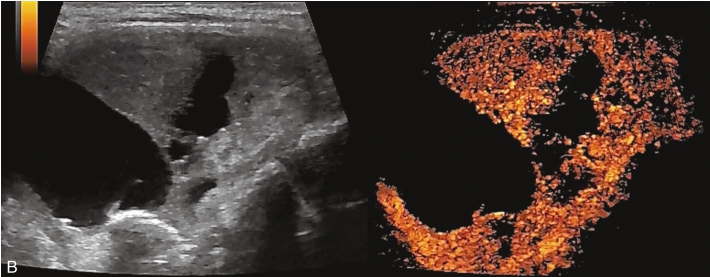

甲状腺左叶中下部见一混合回声结节,边界清,形态规则,中心部可见斑状强回声,CDFI显示周边可见环状血流信号,其内可见丰富血流信号,见图1-3-18。

该结节早于周围腺体组织增强,结节内部呈高增强表现,可见部分无增强区;结节晚于周围腺体组织消退,仍呈高增强表现;结节周边可见均匀高增强环,甲状腺被膜未见明显中断,见图1-3-19、ER1-3-9。

(1)结节增强早期早于腺体增强或与腺体同步增强,增强晚期晚于腺体消退或与腺体同步消退。

(2)结节内部呈均匀或不均匀弥漫性等增强或高增强,增强水平通常高于周围腺体。

(3)结节与周围腺体分界清晰,形态较规则。

(4)部分结节周边可见均匀高增强环。

(5)结节周边被膜连续完整。

甲状腺滤泡性腺瘤通常为富血供病灶,其增强水平等于或高于周围腺体,并呈现“早增强,晚消退”的特点,重点需要与滤泡性腺癌鉴别,腺瘤多边界清晰、形态较规则,造影时结节周围的高增强环厚薄一致、较为均匀,结节周边被膜连续完整、无浸润表现,颈部淋巴结无异常肿大等。而滤泡性腺癌边界不清、呈浸润性生长表现,周边高增强环消失或厚薄不均,如发现颈部异常肿大淋巴结及被膜连续性中断等,需要高度警惕甲状腺恶性肿瘤。

图1-3-18 甲状腺滤泡性腺瘤常规超声声像图

A.甲状腺左叶纵切面超声图像;B.结节内部点状及斑状强回声;C.CDFI血流图